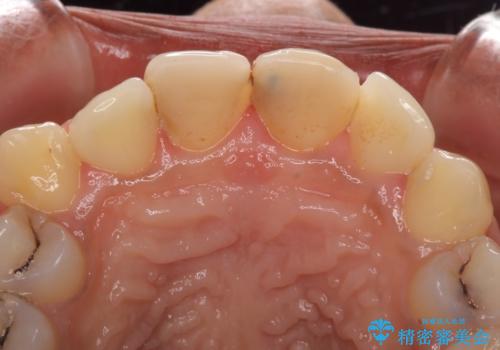

- 上の前歯2本の審美障害を気にして来院された患者様です。樹脂が無造作に充填されており、色合いも形態も不自然で、歯肉も腫れているため、オールセラミッククラウンにて補綴することとしました。

充填されたレジンを取り除いたところ、歯肉の炎症による出血が認められました。セラミッククラウン装着後は歯肉が腫れることもなく、仕上がりも自然な歯のようになり、患者様には大変満足していただきました。